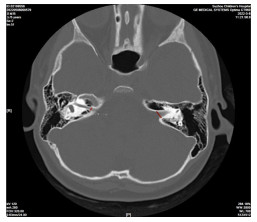

神经超声联合神经磁共振成像在吉兰-巴雷综合征诊断中的意义及机制研究

时鹏, 武心语, 怀玉水, 宋宏伟, 年娣

2025, 23(8): 1292-1297. doi: 10.16766/j.cnki.issn.1674-4152.004118

摘要:

目的  探讨神经超声联合神经磁共振成像在吉兰-巴雷综合征(GBS)患者诊断中的作用及机制。  方法  选取蚌埠医科大学第一附属医院2021年10月—2025年2月被诊断为GBS的患者43例,另选取24例健康体检者作为对照组。依据临床症状、体征及神经电生理检查将患者分为急性炎性脱髓鞘性多发神经根神经病(AIDP)和急性运动轴突性神经病(AMAN)两个亚型组,采用神经超声测量颈神经根、肢体周围神经横断面积(CSA);神经磁共振成像测量颈神经根、腰骶神经根CSA;吉兰-巴雷综合征残疾评分量表(GDSS)评估GBS患者神经功能缺失程度,分析CSA与神经缺损程度之间的相关性;收集外周静脉血,ELISA试剂盒测定外周血中细胞焦亡炎性因子水平。  结果  与对照组相比,AIDP组和AMAN组神经根、肢体周围神经增粗,CSA升高,其中神经超声示3组C5、C6比较差异均有统计学意义(H=20.216,P < 0.001;H=12.452,P=0.002);磁共振成像结果显示,与AMAN组和健康对照组相比, AIDP组患者C4~C8、L3~S1的CSA显著升高,差异均有统计学意义(P < 0.01);周围神经CSA与神经功能缺损程度呈正相关关系(P < 0.05);GBS患者外周血焦亡炎性因子水平较对照组升高,差异有统计学意义(P < 0.05)。  结论  GBS患者神经根和周围神经CSA值升高和神经功能缺损可能与焦亡途径激活导致的炎症级联反应有关,联合神经影像学和炎性因子检测有助于GBS的早期诊断,为GBS诊疗提供新思路。